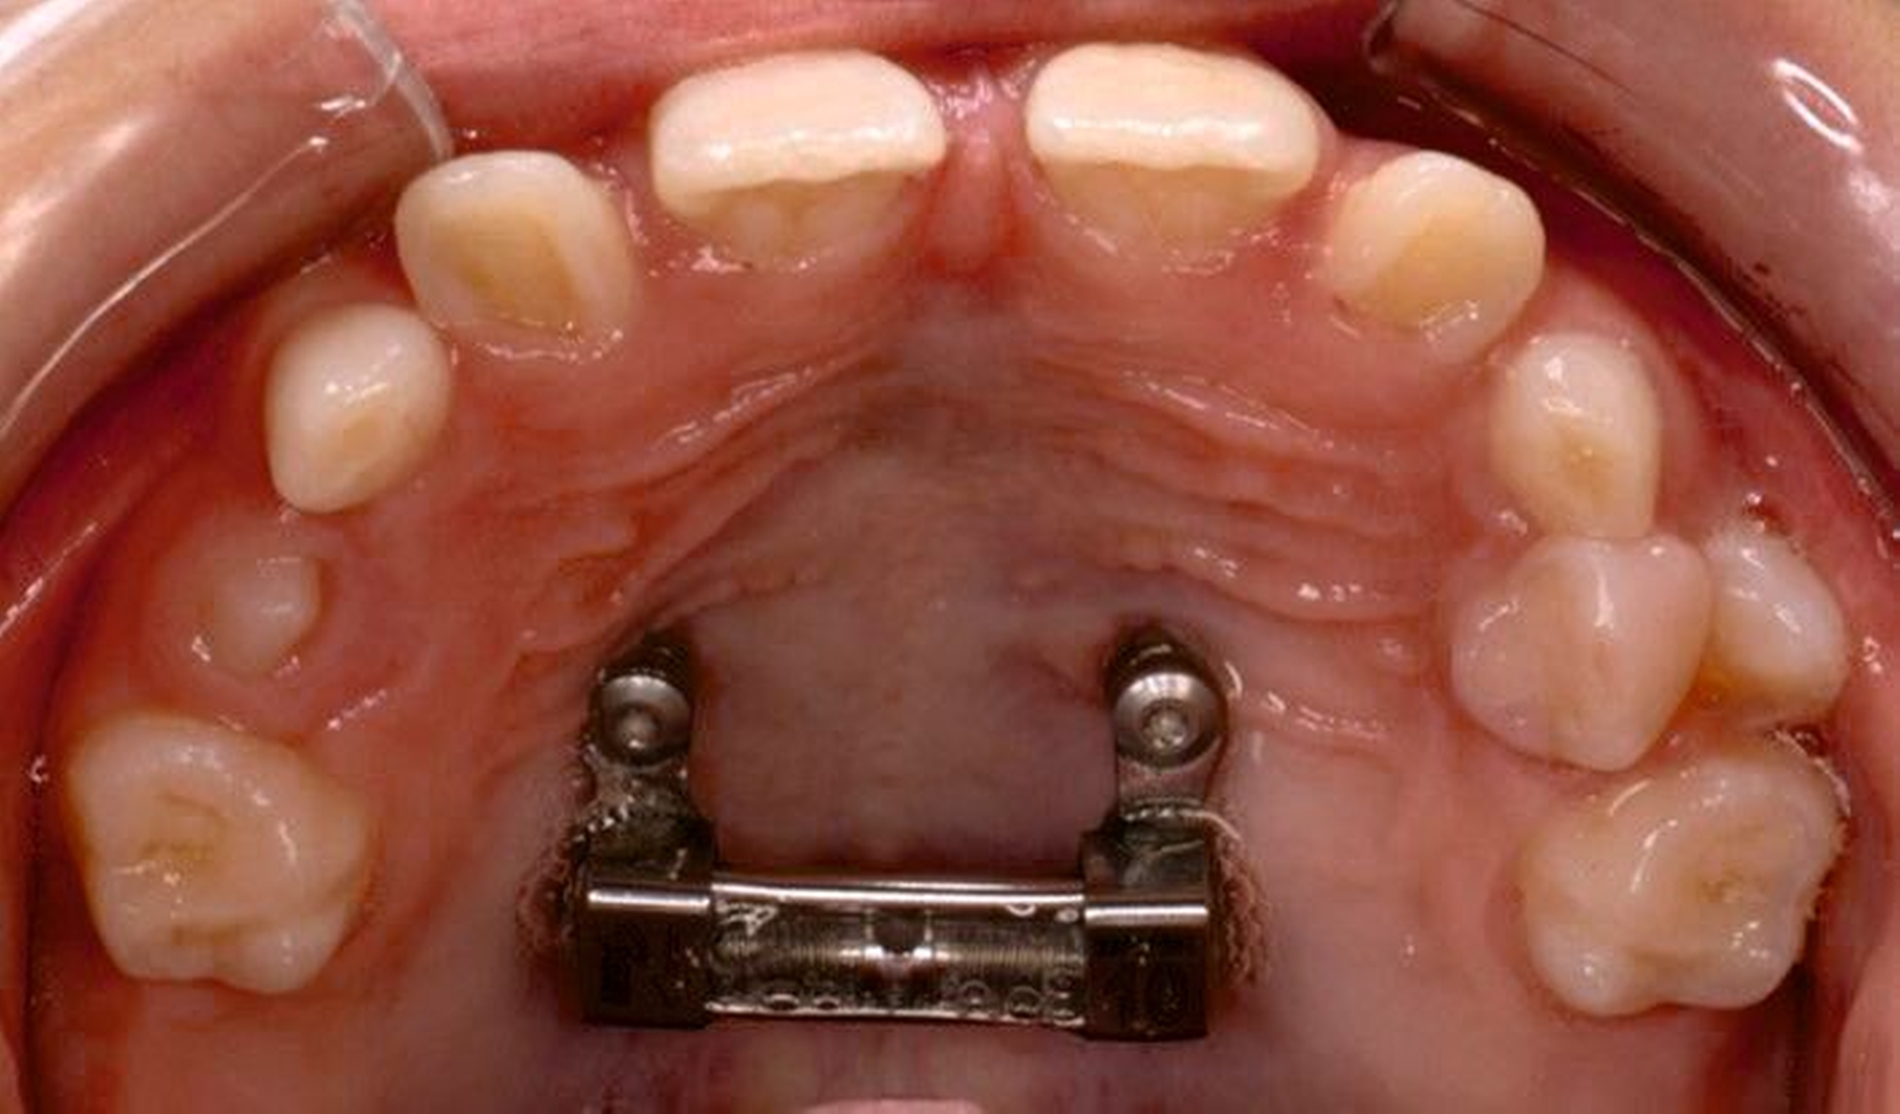

Die Eltern des Patienten wurden angewiesen, die Schraube einmal täglich zu aktivieren. Die gesamte Aktivierungszeit der Hyrax-Schraube betrug circa zehn Wochen. Während dieser Zeit vergrößerte sich die transversale Dimension des Oberkiefers um sieben Millimeter im posterioren Bereich (Milchmolaren) und um fünf Millimeter im anterioren Bereich (Milcheckzähne). Währenddessen trat ein mediales Diastema auf (Abbildungen 4b und 4c), das auf eine skelettale transversale Expansion des Oberkieferknochens hinwies. Nach der aktiven Expansionsphase der Hyrax-Apparatur wurde das Gerät für weitere Behandlungszwecke verwendet: Erstens als Retentionsgerät, um die bereits erzielte transversale Oberkieferbreite zu halten und zweitens als skelettal verankerte Apparatur zum Einstellen der retinierten und verlagerten Zähne mithilfe individuell angefertigter Kragarme. Hierfür wurde die Hyrax-Apparatur im zahntechnischen Labor modifiziert, indem Kreuzröhrchen für eine stationäre Befestigungen für die Drähte des Kragarms angebracht wurden.

Für die Zähne 13, 16, 23 und 26 wurde eine weitere chirurgische Freilegung durchgeführt. Zwei Kragarme (0,017 x 0,025 Zoll TMA-Draht, Dentaurum, Ispringen, Deutschland) wurden verwendet, um die Zähne 13 und 23 kieferorthopädisch in den Zahnbogen einzustellen. Danach wurde eine Teil-Multi-Bracket-Apparatur eingesetzt, um die eruptierten Zähne zu nivellieren (Abbildung 5b). Nach einer Behandlungsdauer von circa sechs Monaten waren die chirurgisch freigelegten Zähne optimal eingeordnet (Abbildungen 5c und 5d). Um die Lücke für die noch retinierten Prämolaren 15 und 25 zu öffnen, wurden in dieser Region auf den Teilbögen offene Federn angebracht. Danach wurden die Zähne 15 und 25 chirurgisch freigelegt und ebenfalls mithilfe von zwei Kragarmen (0,017 x 0,025 Zoll TMA-Draht) eingestellt (Abbildungen 5e und 5f, Abbildung 6).